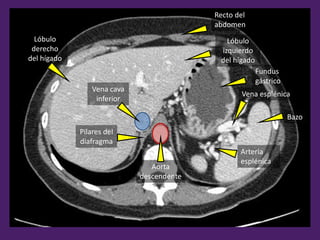

Aorta

descendente

Vena cava

inferior

Lóbulo

derecho

del hígado

Recto del

abdomen

Fundus

gástrico

Bazo

Arteria

esplénica

Vena esplénica

izquierdo

Pilares del

diafragma